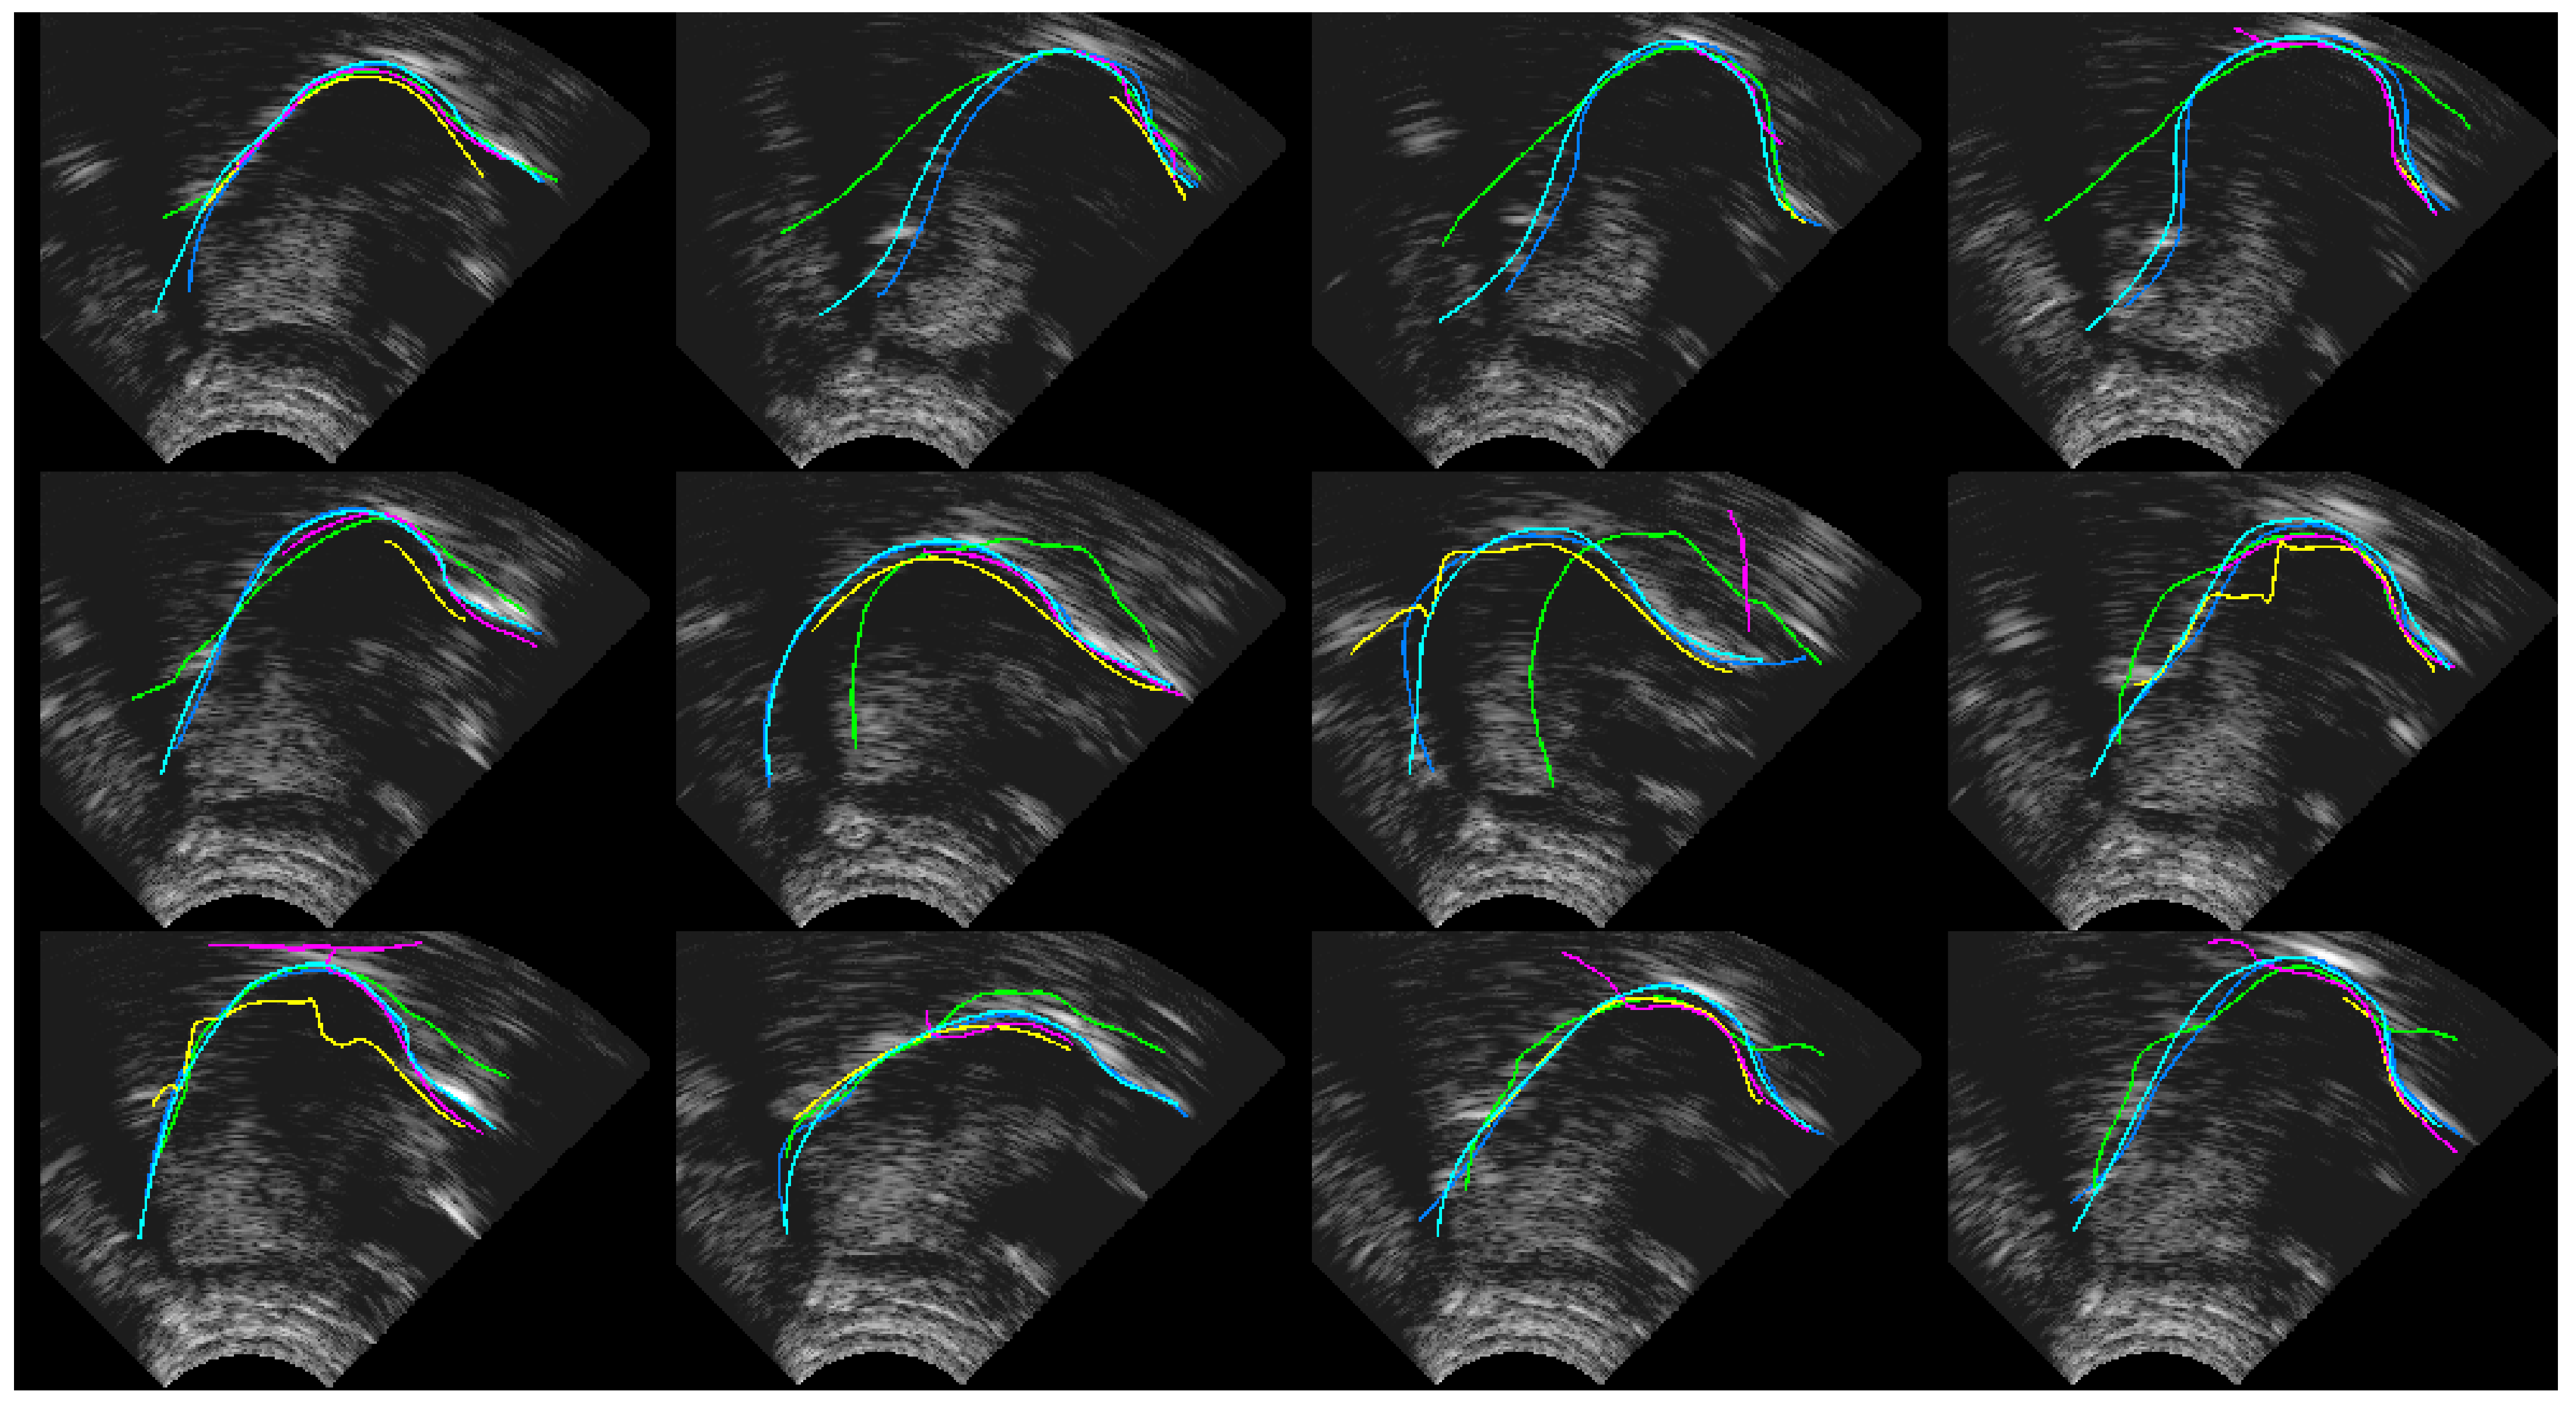

4.1. Ultrasound Contour Tracking